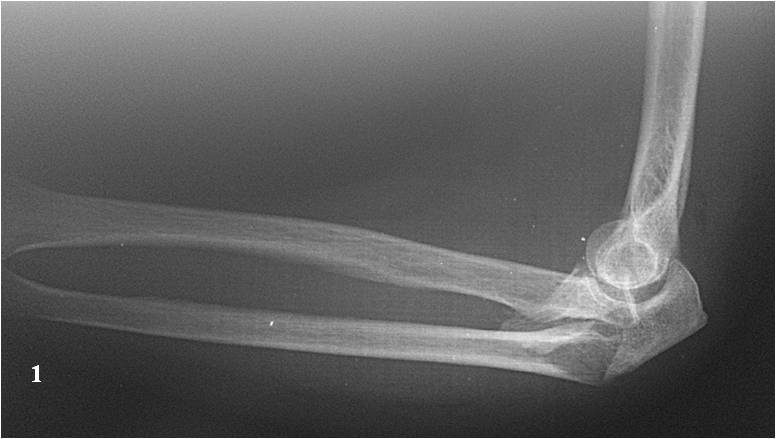

Хочу попросить совета у сообщества по поводу следующего клинического случая. Женщина, 65 лет. Закрытый перелом Монтеджи слева в октябре 2013 года. (рис. 1, 2). Для наглядности сделал скиаграмму перелома (рис. 3, 4). На 8-е сутки накостный остеосинтез пластинами с угловой стабильностью. Головка луча была восстановлена из отломков (рис. 5) и собрана на спицах одну из которых скусили и оставили под пластиной.(рис. 6). Вроде получилось стабильно, видео на операции по этой ссылке: